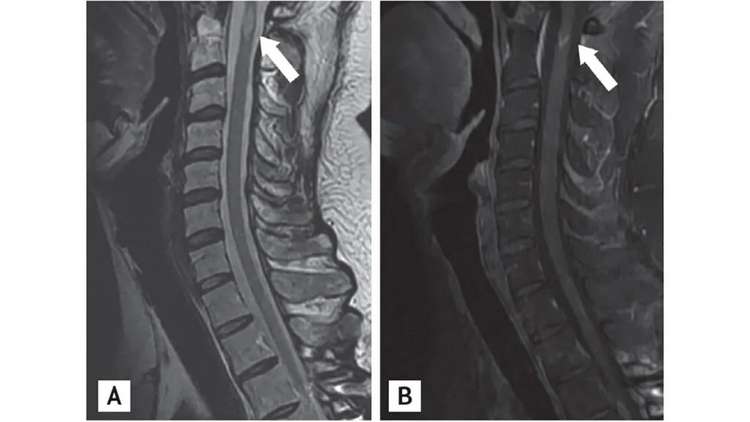

The patient is therefore admitted to the neurology department. Here the neurological evaluation with MRI of the brain and spinal cord with contrast medium is continued. This examination shows multiple periventricular, juxtacortical and infratentorial hyperintense lesions in T2/FLAIR. Some of these lesions enhance with contrast, others do not, suggesting dissemination over time. A single demyelinating lesion is present at the cervical level (C3-C4).

Images of MS Lesions on the ..

Images of MS Lesions on the spine, via x ray. Image Credit: Yoon BN, Ha CK, Lee KW, Park SH, Sung JJ. A confusing case of multiple sclerosis and central nervous system graft versus host disease. Korean J Intern Med. 2016;31(5):995-998. doi:10.3904/kjim.2015.065